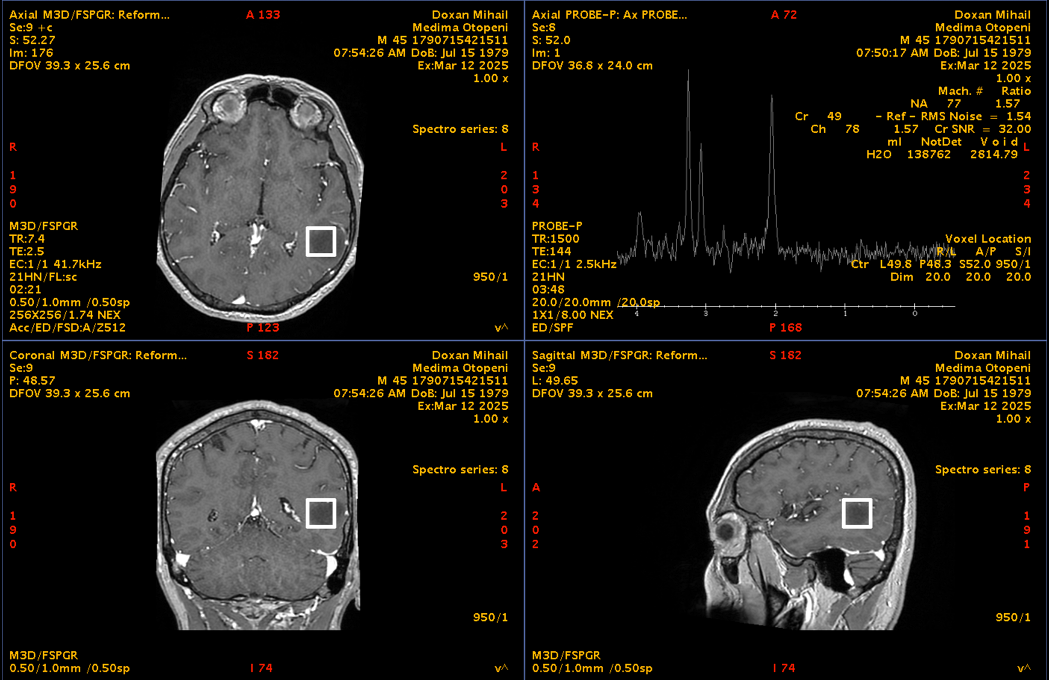

RMN cerebral cu contrast – metoda standard pentru caracterizarea glioamelor. Glioamele de grad mic apar ca leziuni hipointense pe T1, hiperintense pe T2, fără captare de contrast. În mod uzual se consideră că dacă un gliom de grad mic are o zonă cu priză de contrast pe RMN el este de grad III – anaplazic (grad înalt).

Spectroscopie RMN și perfuzie cerebrală – pot oferi informații suplimentare despre agresivitate.

Oligodendrogliom temporal stâng – spectroscopie RMN